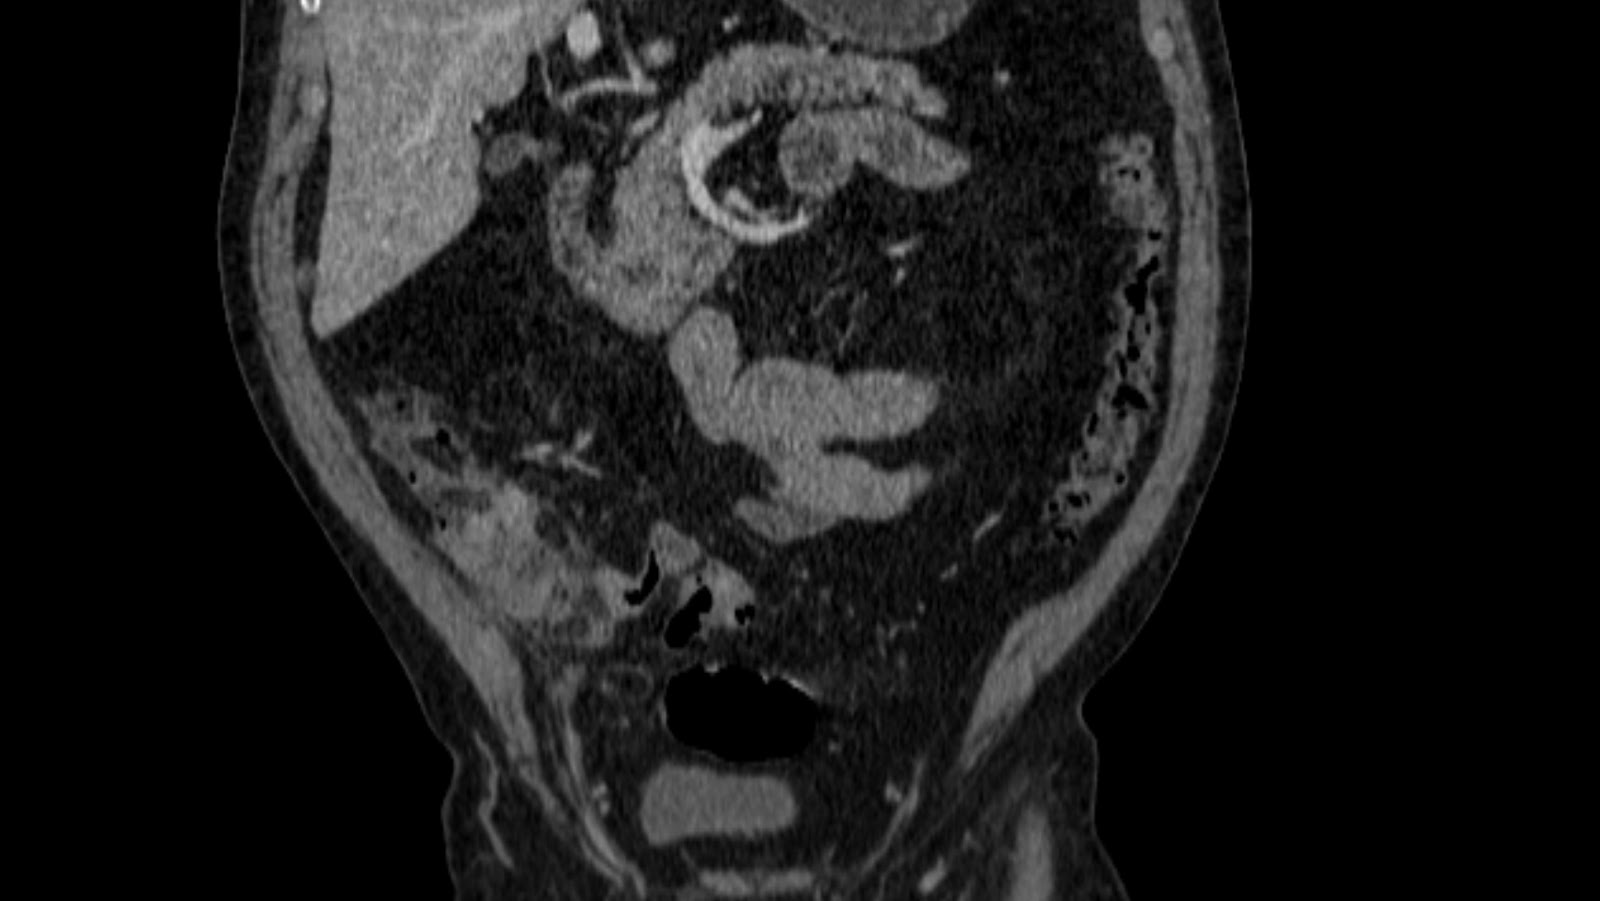

Radiografía de tórax: masa redondeada de gran tamaño que parece proceder de mediastino anterior con imagen en suelta de globos. TAC Abdomen-pelvis: extensa masa localizada en mediastino anterosuperior, heterogénea con múltiples zonas hipodensas en probable relación a necrosis.. El coriocarcinoma se incluye dentro de los no seminomas.

La radiografía de tórax muestra imágenes nodulares múltiples en ambos campos pulmonares («en suelta de globo») , TAC toracoabdominal confirma los nódulos pulmonares bilaterales, adenopatías mediastínicas anteriores, precarinales y retroperitoneales que desplazan vena porta.